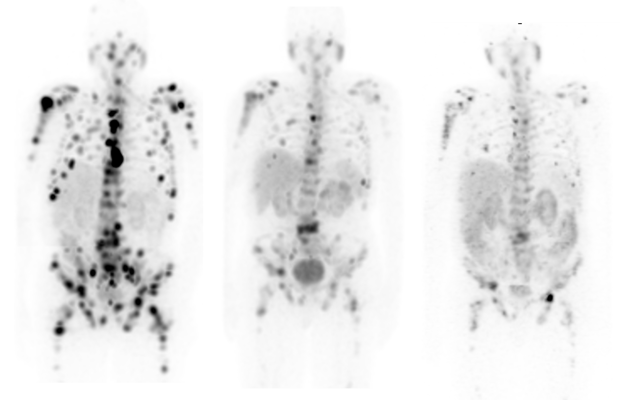

Diagnosis: Accurately Staging & Quantifying Disease: To read the emissions released by the Gallium-68 PSMA-11 tracer, the patient must be imaged using a highly sensitive PET/CT scanner. This technology provides the clinician detailed information that is used to better understand the structure and function of each patient’s tissue and disease state to help form personalized therapy recommendations. The more sensitive the PET/CT, the more accurate the images and quantification.

To this end, GE Healthcare is now shipping its Discovery MI Gen 2 premium digital PET/CT system, which provides next-level digital detection with an axial field of view (FOV) scalable up to 30 centimeters to achieve a 125 percent increase in sensitivity[v]. This helps translate to 33 percent improvement in scan times or dose amounts[vi].

These capabilities are further supported by Q.Clear, which offers up to 2x improvement in both image quality (SNR) and quantitation accuracy (SUV[vii]), and MotionFree for up to 67 percent improvement in lesion volume measurements, helping inform clinicians’ prostate cancer therapy recommendations[viii].

Additionally, this scanner includes a CT that is designed to allow TrueFidelity deep-learning image reconstruction to enable image sharpness and improved noise texture[ix],[x]. Discovery MI Gen 2 proclaims up to a 41 percent increase in small lesion detectability[xi].

To help clinicians evaluate the success of these therapies, GE Healthcare developed its breakthrough StarGuide SPECT/CT system with 12 cutting-edge CZT detectors that not only scan patients in 3D to provide more information to clinicians but are also optimized for Theranostics procedures – including imaging this latest Lutetium-177-based prostate cancer therapy.

Compared to conventional technologies, StarGuide’s Digital Focus CZT detectors offer improved volume sensitivity and SPECT resolution[xiii], which is especially valuable for imaging both peaks of Lutetium-177 emissions, which in turn helps clinicians pinpoint the size, shape, and position of lesions with exceptional accuracy. Paired with GE Healthcare’s innovative Q.Clear solution for SPECT reconstruction, the resulting images provide outstanding quantification for the diagnosis and staging of disease and monitoring of treatment.